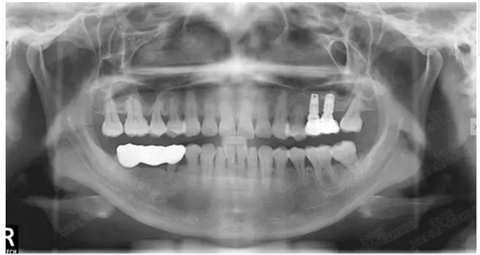

病例四

剩余骨量2mm-5mm且存在斜形竇底

007.png

提升8mm

008.png

009.png